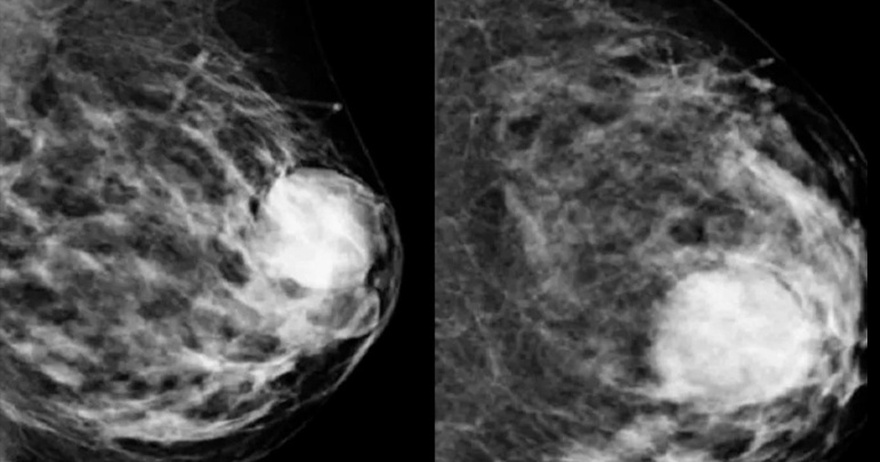

Το καρκίνο του μαστού είναι ένας τύπος καρκίνου που ξεκινά με την ανάπτυξη κυττάρων στον ιστό του μαστού. Μετά τον καρκίνο του δέρματος, ο καρκίνος του μαστού είναι ο πιο συχνά διαγιγνωσκόμενος καρκίνος στις γυναίκες στις Ηνωμένες Πολιτείες. Ωστόσο, ο καρκίνος του μαστού δεν αφορά μόνο τις γυναίκες. Όλοι έχουμε κάποιον ιστό μαστού, οπότε οποιοσδήποτε μπορεί να εμφανίσει καρκίνο του μαστού. Ας εξερευνήσουμε τα συμπτώματα και τις αιτίες του καρκίνου του μαστού.

Πολλά από αυτά τα σημάδια μπορεί να οφείλονται και σε καλοήθεις (μη καρκινικές) παθήσεις του μαστού. Τα συμπτώματα αυτών των καταστάσεων μπορεί να περιλαμβάνουν ογκίδια, πόνο ή έκκριση από τις θηλές. Κάποιες καλοήθεις καταστάσεις μπορεί να φανούν σε μαστογραφία.